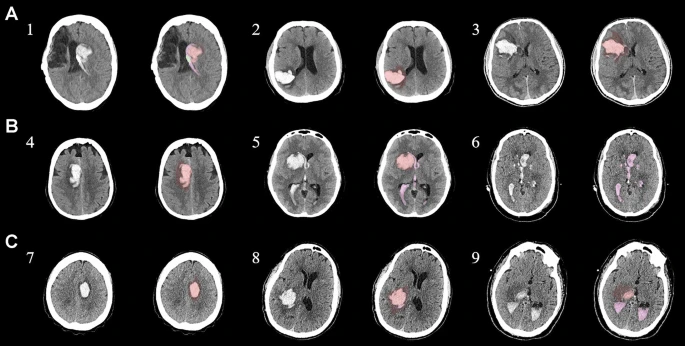

為了描述目的,患者按入組順序被賦予編號,并被連續(xù)分配到三組中的一組,每組三名。根據(jù)模型2分割,ICH體積范圍為0.1至54.9mL(平均ICH體積為23.5mL)。5名ICH患者受累于局限性腦葉,其余患者受累于基底神經(jīng)節(jié)或外囊深處。3名患者的ICH位于丘腦(圖1),1名患者的血腫位于多個(gè)腦結(jié)構(gòu)(即尾狀核、殼核和蒼白球)。平均而言,MSCs是在ICH后3天注射的。

結(jié)合臨床特征的探索性成像容積模型分析

ABC/2模型1和模型2分割方法均通過線性回歸顯示出ICH和IVH體積的良好相關(guān)性(圖3a、b)。與模型2分割體積方法(例如每CT15-20分鐘)相比,模型1ABC/2衍生的半定量方法和改進(jìn)的Graeb IVH方法所需的時(shí)間更短(例如2-5分鐘)。有趣的是,將NIHSS評分與IVH體積M2方法進(jìn)行比較顯示出線性相關(guān)性(R2=0.7217),并且當(dāng)IVH小于20mL或大于20mL時(shí),NIHSS評分似乎存在聚集性(圖3c)。PHE 分析顯示MSC注射劑量與PHE體積之間存在輕微的負(fù)相關(guān)關(guān)系。